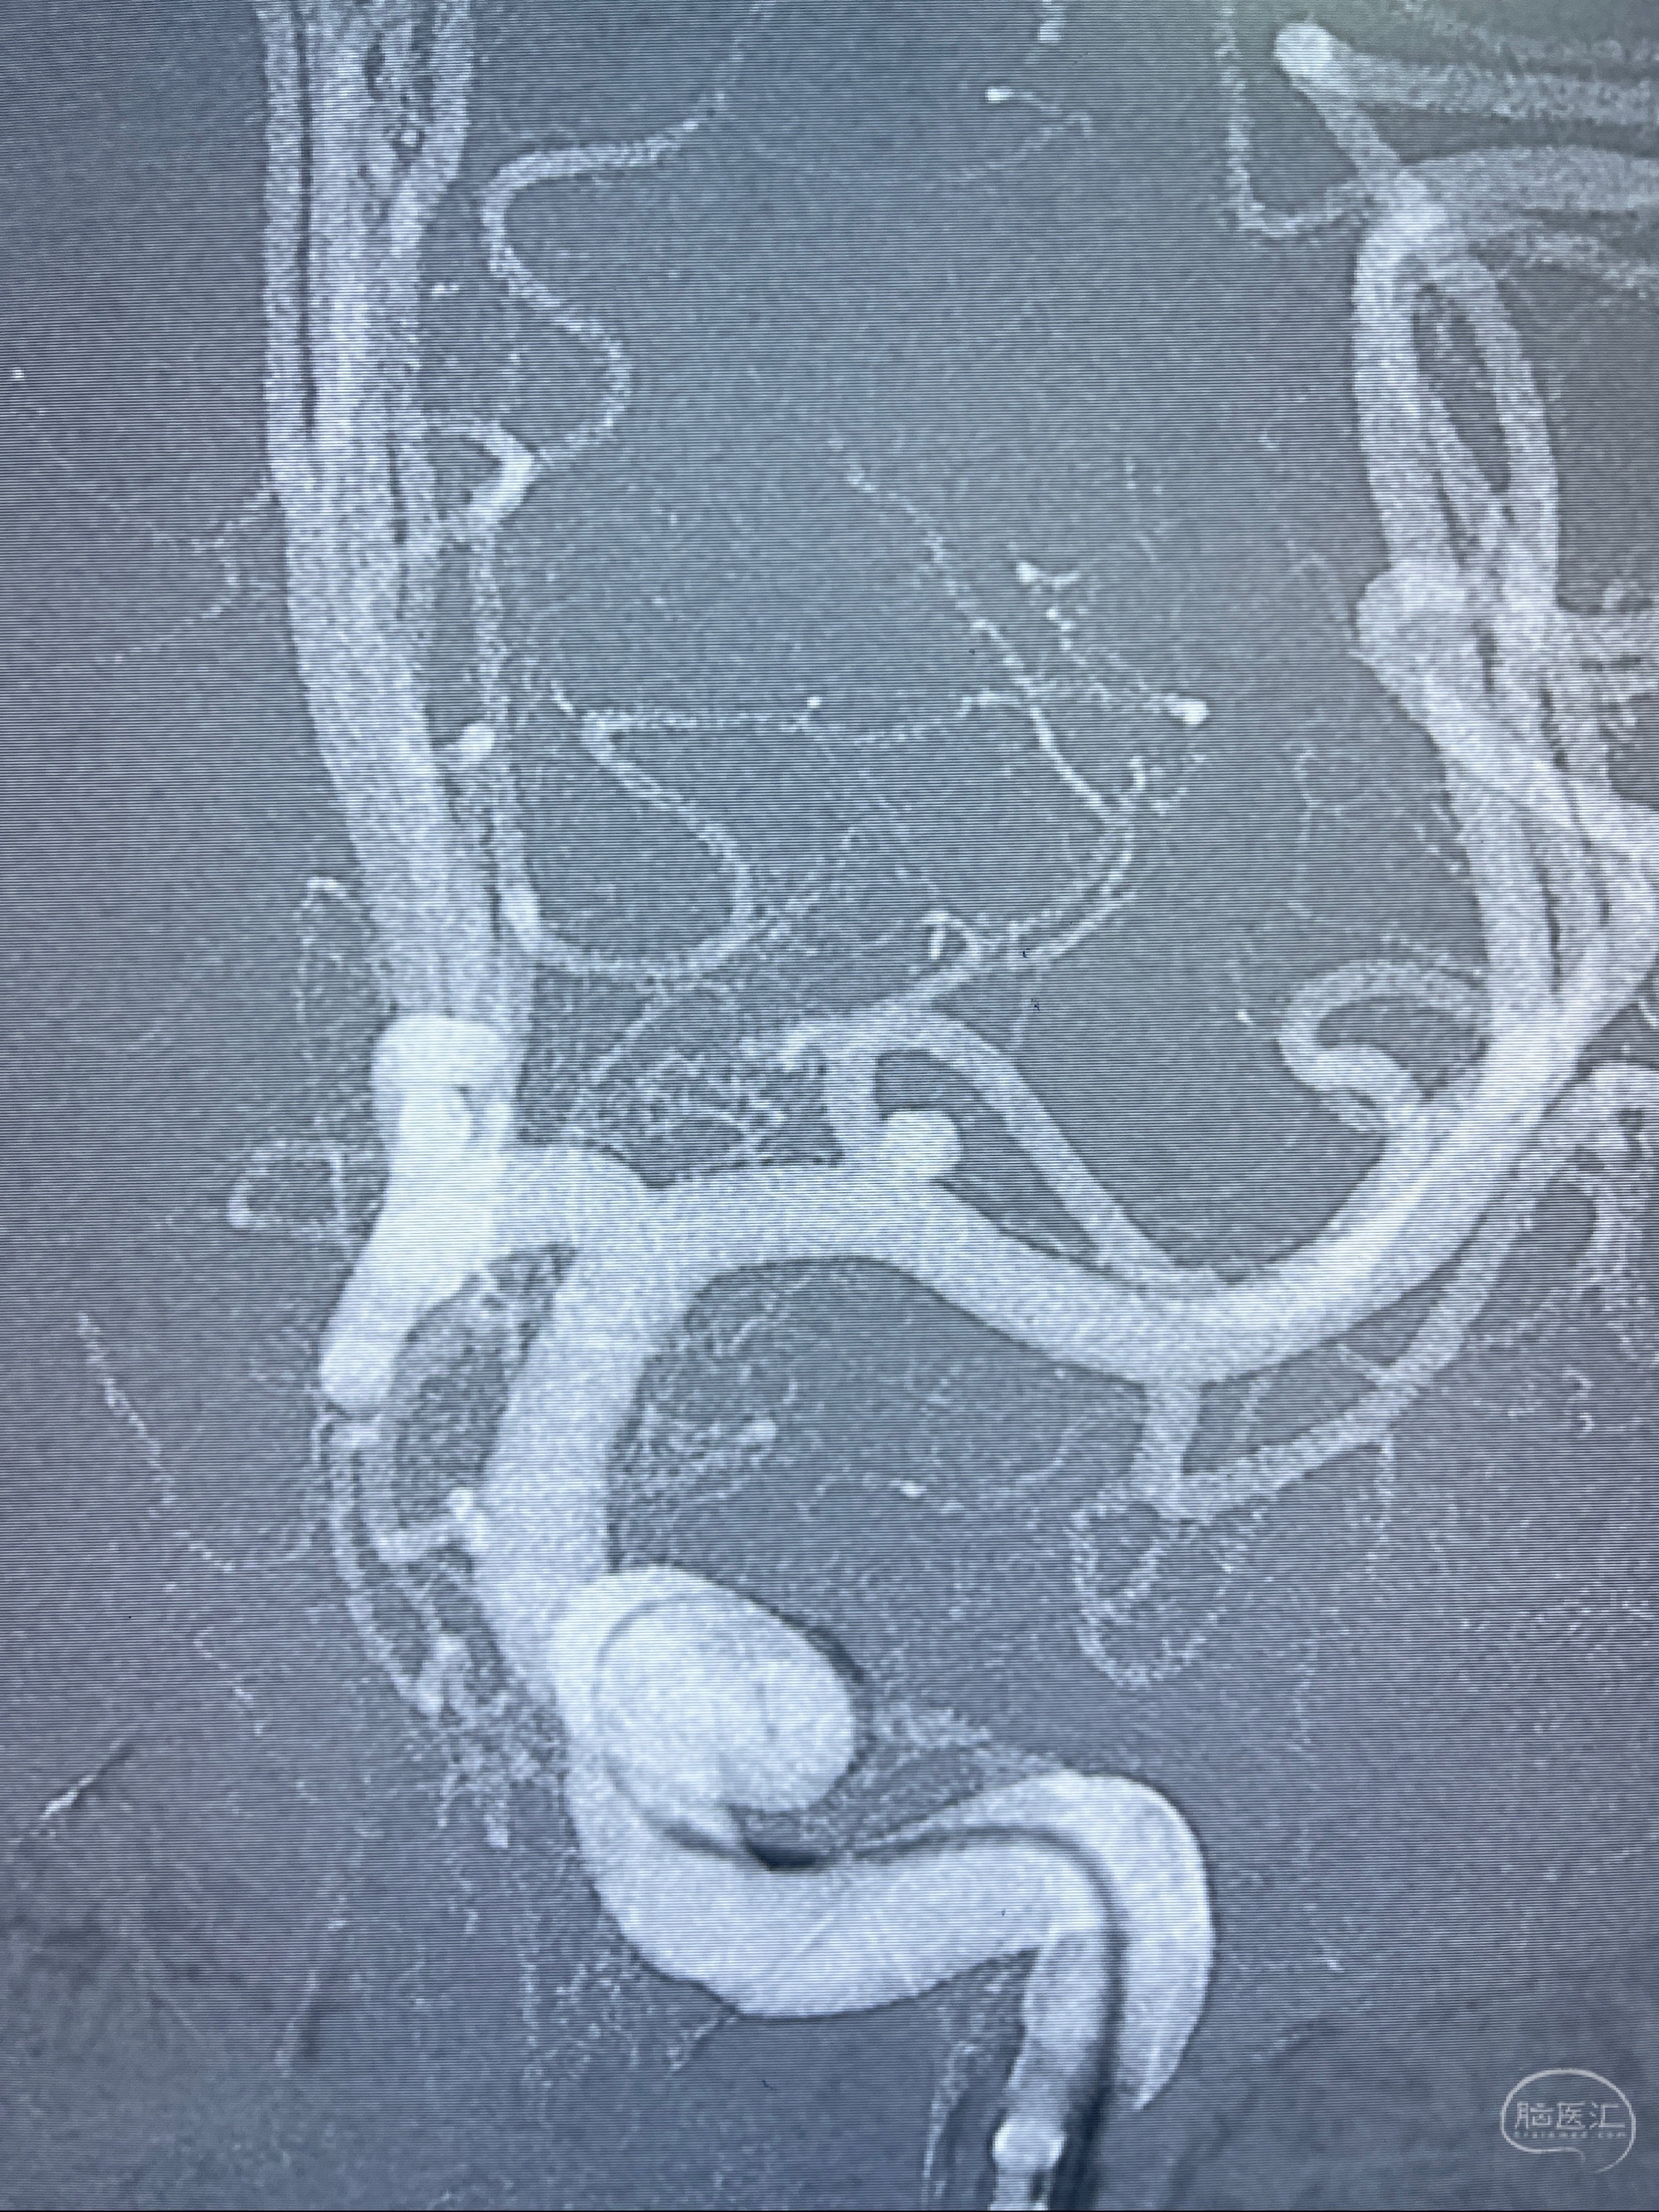

2023-08-14DSA:

左侧大脑中动脉动脉瘤,约2.6-2.8-3.4-2mm大小(瘤颈部、瘤体部、瘤高)

1.左侧大脑中动脉动脉瘤,约2.6-2.8-3.4-2mm大小(瘤颈部、瘤体部、瘤高)

2.外科手术夹闭or介入支架辅助栓塞